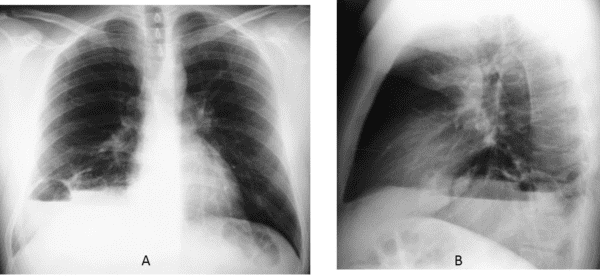

Phổi biệt lập

Phổi biệt lập - Ảnh 2

Phổi biệt lập - Ảnh 3

» Thông tin: Nam giới – 41 tuổi.

» Lâm sàng: Viêm phổi tái phát.